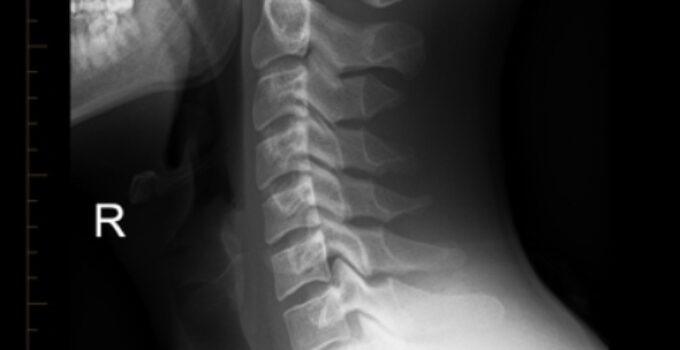

Boyun röntgeni, boyun bölgesindeki kemik, eklem ve yumuşak dokuların detaylı bir şekilde incelenmesini sağlayan önemli bir medikal görüntüleme yöntemidir. Bu yazıda, boyun röntgeni nedir, nasıl yapılır, hangi durumlarda uygundur gibi konuları detaylı bir şekilde ele alacağız.

Boyun röntgeni, boyun bölgesindeki anatomik yapıları görmek için kullanılan bir radyolojik inceleme yöntemidir. Genellikle boyundaki kemikler, eklem yapıları, diskler ve yumuşak dokuların durumu değerlendirilir.

Boyun röntgeni sonuçları, bir radyolog tarafından incelenir ve raporlanır. Bu değerlendirme sırasında boyundaki kemik yapısı, eklemler, diskler ve diğer yapılar gözlemlenir.